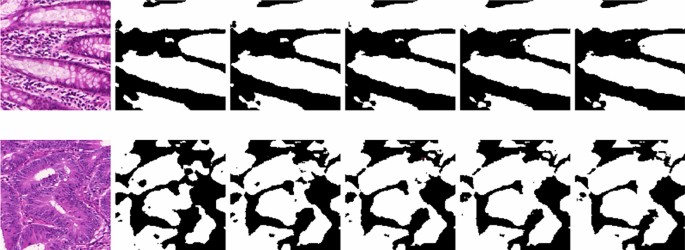

We have also visualized the pseudo-labels generated by the proposed model for every iterations and has been shown in Fig. 6. It can be seen that, over the iterations, the quality of the pseudo-labels have improved. Further, the false positives generated by the proposed model is reduced which are highlighted in the figure. This further validates the benefits of self-supervised learning for training the teacher model.

Evaluation of pseudo-labels

Evaluating the quality of pseudo-labels produced by the teacher model is crucial to ensure that they are reliable and useful for training the student model. In the present study, we have set \(\tau =0.7\). An experiment is carried out for evaluating the reliability of pseudo-labels produced by the teacher model. To this end, we have visualized the pseudo-labels, as shown in Fig. 6. Furthermore, we have also performed uncertainty estimation using the Monte Carlo (MC) Dropout technique. The approach includes conducting numerous forward passes through the network while enabling dropout during inference. Initially, we train the teacher model incorporating dropout layers. Unlike standard practice where dropout is disabled during inference, for MC Dropout, dropout is kept enabled during inference. This is crucial for generating diverse predictions for the same input. Pass the input data through the network multiple times (e.g., 30 or more forward passes), each time with dropout enabled. This will result in a set of different predictions due to the stochastic nature of dropout. By analyzing the model’s predictions, we can gain valuable insights into its performance.